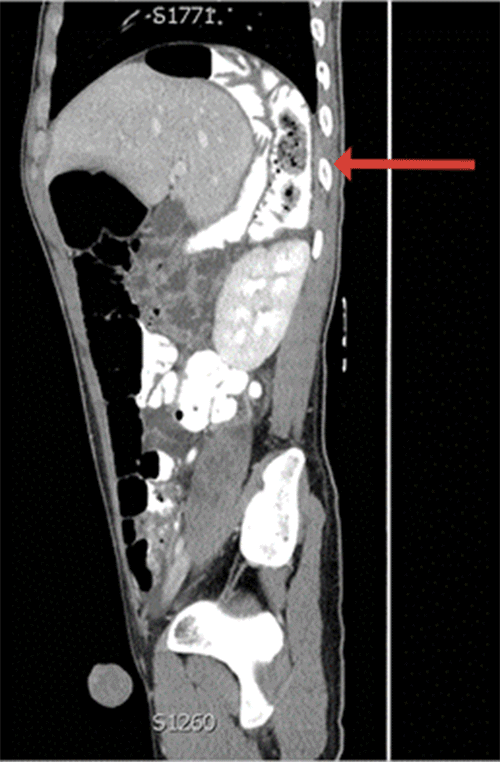

One week after last discharge, the patient returned for the fourth time with recurrent symptoms. Admission CT scan demonstrated Chilaiditi 's sign as well as a twisted proximal colon posterior to the liver (Figure 4). After recommending colectomy to prevent recurrence, the patient agreed to proceed to the operating room.

Figure 4. CT Scan on Fourth Presentation. Published with Permission

A (sagittal), Hepatic flexure interposed posteriorly and medially to the right liver lobe; and B (coronal), hepatic flexure interposed posterior and medial to the right liver lobe, consistent with Chilaiditi syndrome